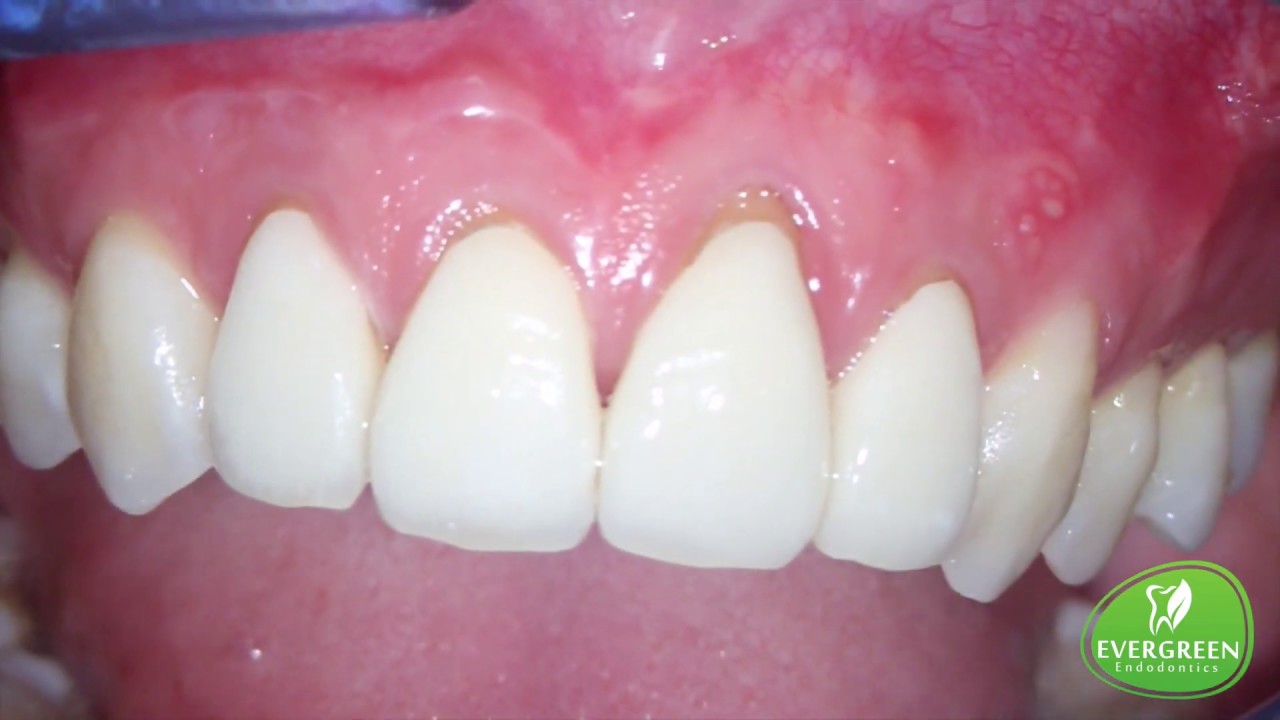

From www.youtube.com

Endodontic Microsurgery (Apicoectomy) on Tooth 12 & 13 Evergreen Apicoectomy And Endodontic eliminate persistent endodontic pathogens: apicoectomy, often deemed a last resort in endodontic treatments, is a fascinating procedure. an apicoectomy is a common dental procedure where inflamed gum tissue and the end of the root of your tooth is. While not as commonly discussed as root canals or tooth extractions, it holds a special place in dental care.. Apicoectomy And Endodontic.